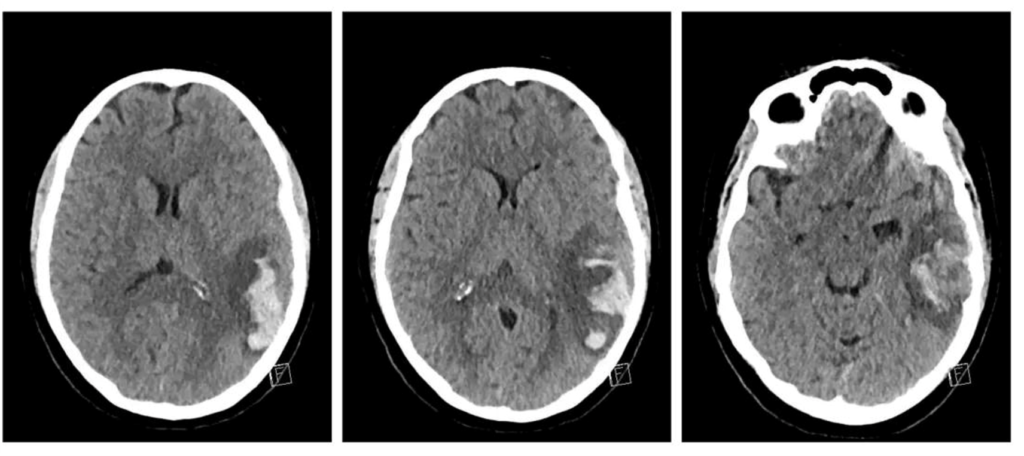

NCCT: Hemorrhagic infarct of left temporal lobe

This infarct is anatomically adjacent to two temporal lobe venous sinuses.